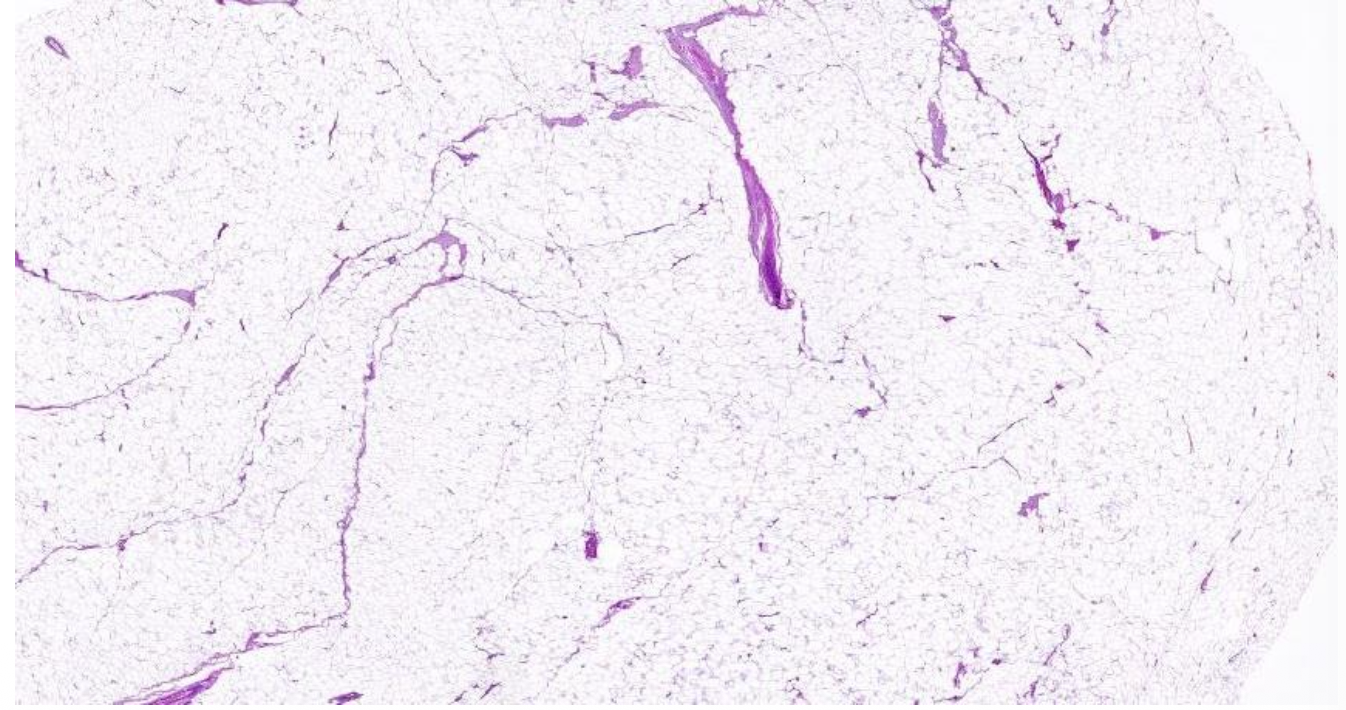

welk type tumor

lipoom

pathologische kenmerken lipoom

mature adipocyten

fijne fibreuze septa

vascularisatie